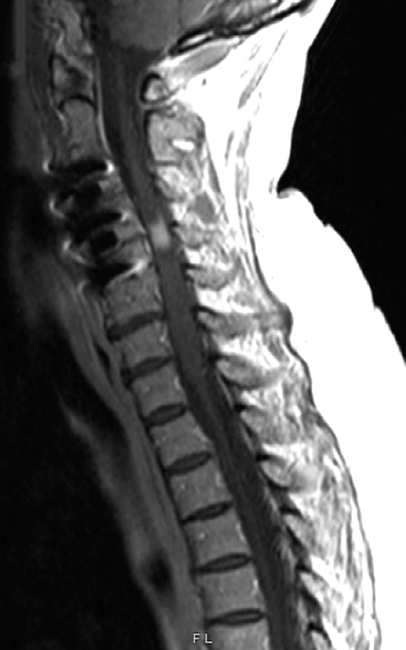

Q7: A 75-year-old woman with history of prior cervical spine decompression presented with progressive neck pain, asymmetric hand tingling, and neuropathic pain, followed by urinary incontinence and gait difficulty. Sagittal T2 weighted imaging likely shows?.